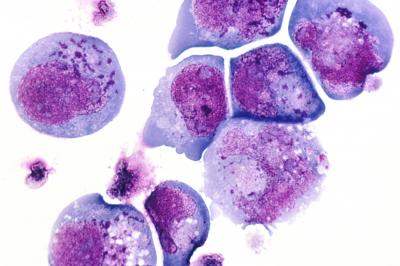

The same viruses that make us sick can take up residence in and on the human body without provoking a sneeze, cough or other troublesome symptom, according to new research at Washington University School of Medicine in St. Louis. On average, healthy individuals carry about five types of viruses on their bodies, the researchers report online in BioMed Central Biology. The study is the first comprehensive analysis to describe the diversity of viruses in healthy people.

In 102 healthy young adults ages 18 to 40, the researchers sampled up to five body habitats: nose, skin, mouth, stool and vagina. The study's subjects were nearly evenly split by gender.

At least one virus was detected in 92 percent of the people sampled, and some individuals harbored 10 to 15 viruses.

Analyzing the samples, the scientists found seven families of viruses, including strains of herpes viruses that are not sexually transmitted. For example, herpesvirus 6 or herpesvirus 7 was found in 98 percent of individuals sampled from the mouth. Certain strains of papillomaviruses were found in about 75 percent of skin samples and 50 percent of samples from the nose. Novel strains of the virus were found in both sites.